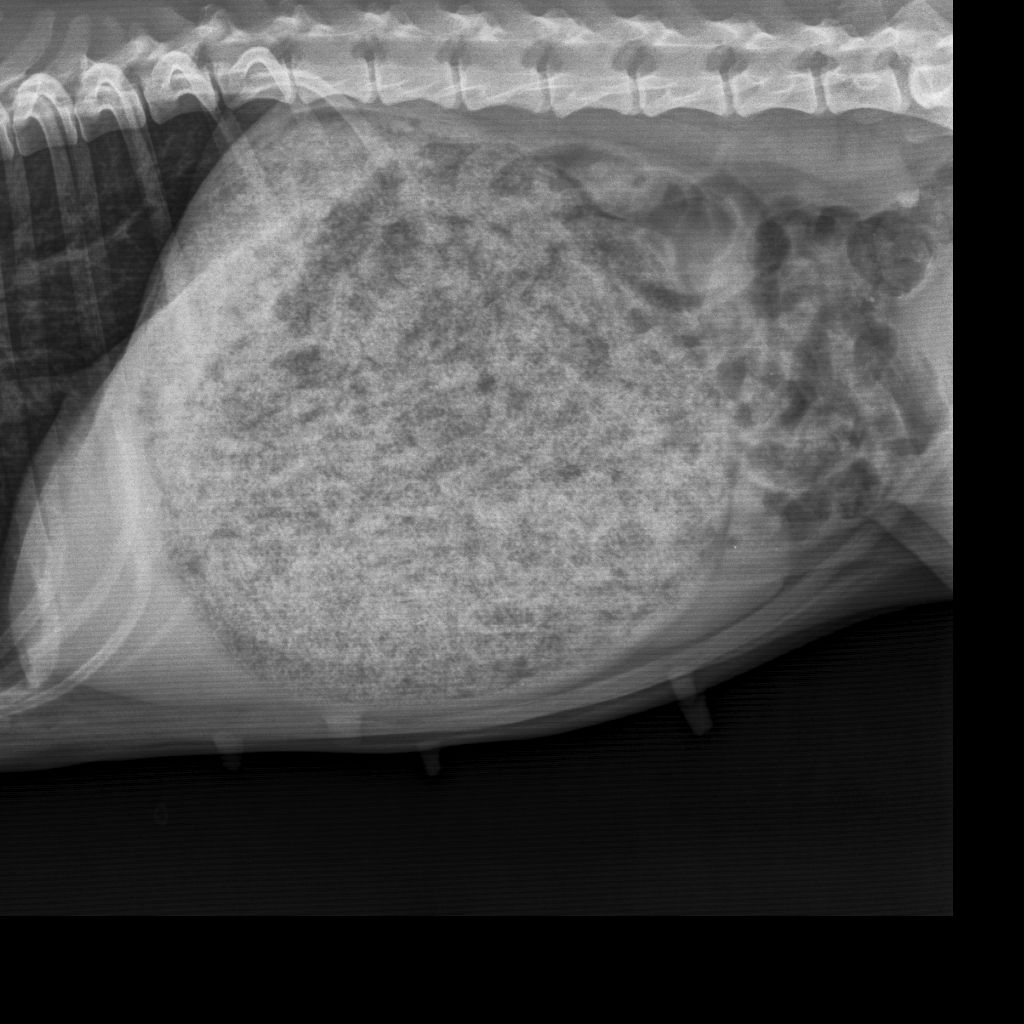

• Abdominal- und Thoraxröntgen

• Trächtigkeitsuntersuchungen